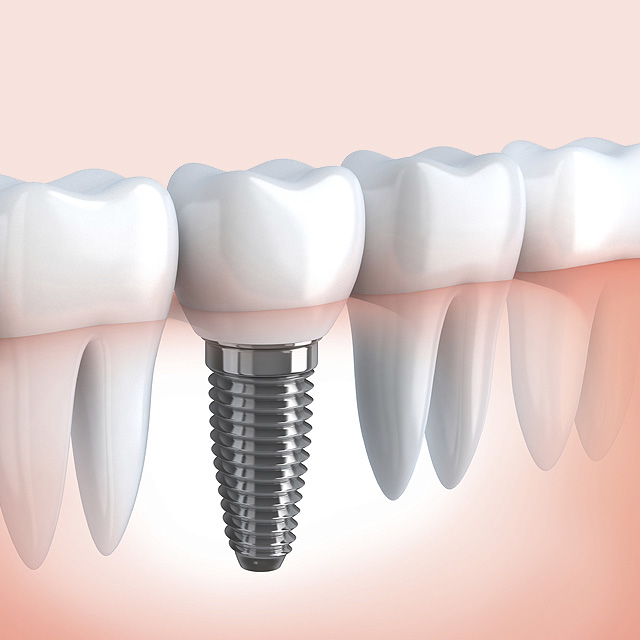

implantes Dentários

É uma raiz artificial, normalmente de titânio, introduzidos cirurgicamente nas áreas desdentadas. Assim permitindo ao dentista instalar dentes artificiais de porcelana ou acrílico sobre eles (Prótese Dentária).